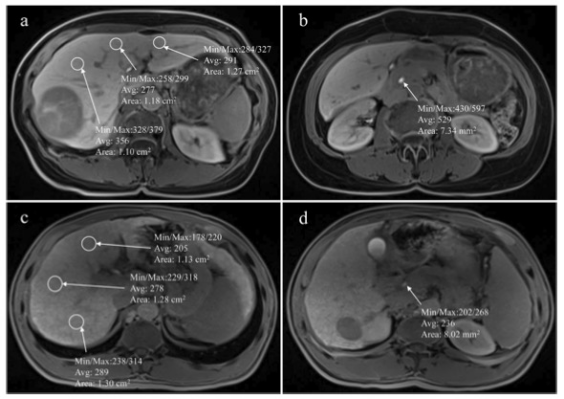

圖 MR圖像顯示了在肝膽期測量肝臟和膽道系統的信號強度感興趣區域的位置。a和b選自一名沒有出現肝切除術后肝衰竭的患者。c和d選自一名肝切除術后出現肝衰竭的患者